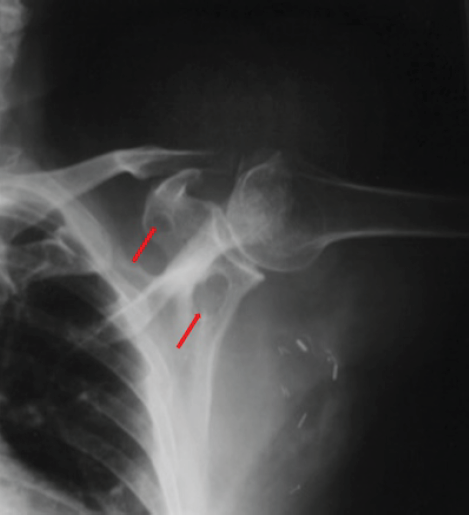

A 79-year-old woman presented with a complaint of a non-painful soft tissue mass in the left axilla of 2-month duration. An incomplete resection of the mass was performed at another institution 6 months before presentation. The histopathologic interpretation of this mass at the outside hospital was that of a low-grade well-differentiated liposarcoma, likely referred to what is now named an atypical lipomatous tumor. On physical examination, there was a large, deep mobile, and non-tender mass adjacent to the chest wall and lateral to the scapula. There was another large, non-tender, bulging mass overlying the posterior surface of the left scapula that did not appear on examination to be contiguous with the axillary mass. The patient was unaware of the posteriorly based mass. An AP radiograph showed focal, well-defined radiolucent defects in the neck and spine of the scapula (Fig. 4). CT and MRI showed a large, multilobulated soft tissue mass around the posterior aspect of the scapula and deep to the supraspinatus and infraspinatus muscles. The mass perforated the scapula from posterior to anterior and extended laterally into the axilla; it was contiguous with the axillary mass (Fig. 5a and b). The portion of the mass over the posterior aspect of the scapula was homogenous and hyperintense on T1 and T2 pulse-weighted sequences, whereas the axillary mass was more heterogeneous and somewhat more hypointense on T1 pulse-weighted sequences.

Figure 4: Case 3 radiograph – anteriorposterior (AP) view. AP radiograph demonstrates focal well-defined radiolucent defects in the neck and spine of the scapula (red arrow).